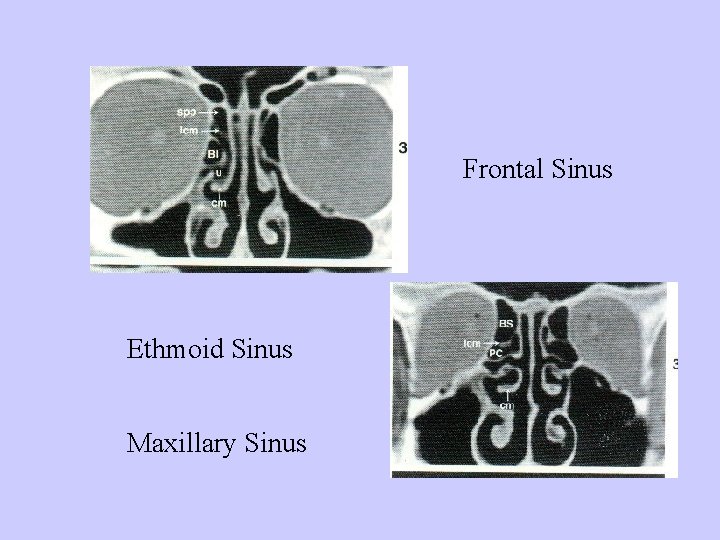

Sinusitis Acute suppurative sinusitis Features of sinus anatomy: 1、small ostia of the sinuses; 2、continuative mucosa between nasal cavity and sinuses; 3、contiguous of the ostia; 4、location of the astia and features of the sinuses.

Frontal Sinus Ethmoid Sinus Maxillary Sinus